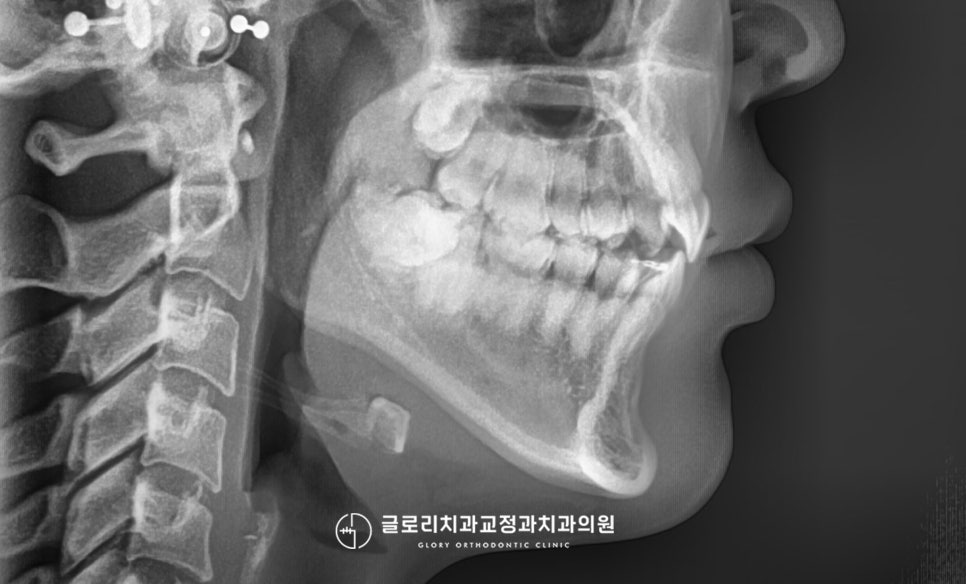

문제점부터 하나씩 차근차근 살펴보면,

윗니 전치부의 가운데의 인접치로 측절치가

유독 이동한 모습이 눈에 띄었습니다.

앞으로 뻐드러짐과 동시에

살짝 회전된 듯한 형태도 보이는데요.

측면에서 보게 되면 이런 뻐드러짐이

더욱 눈에 띄어 튀어나온 듯한 느낌이 듭니다.